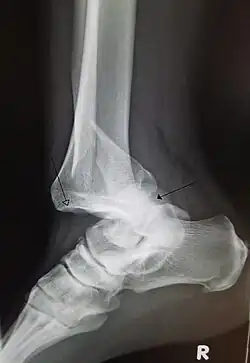

Radiograph of right fifth phalanx bone dislocation -